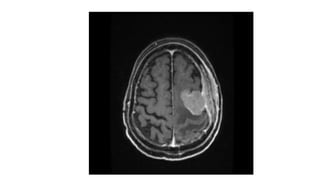

• Multiplaner sagital ,coronal and axial images show a well defined ,midline, broad dural based,

lobulated T1WI iso , T2WI iso to slightly hyper and FlAIR hyperintense mass noted in suprasellar

area having extension forwards along the planum sphenoidale and backwards along the dorsum

sellae.

• After IV contrast avidly homogenous enhancement of the lesion and adjacent linear dural

enhancement over the clivus and planum sphenoidale representing dural tail are noted.

• The lesion causing compression over the optic chiasma, pituitary gland and floor of 3rd ventricle,

and encasing the supraclinoid ICA, ACA and MCA of both sides.

• The mass effect is evidenced by obliteration of Suprasellar & interpeduncular cysterns and

symmetrical indentation of underlying cerebral cortex.

• No perilsional edema is noted

• However lateral , 3rd and 4rth ventricles appear normal

• Complementary CT cut was taken and showing iso to slightly hyperdense lesion. No calcification is

noted. Bone CT shows bony hyperostosis at planum sphenoidale .Sellar size is within normal limit